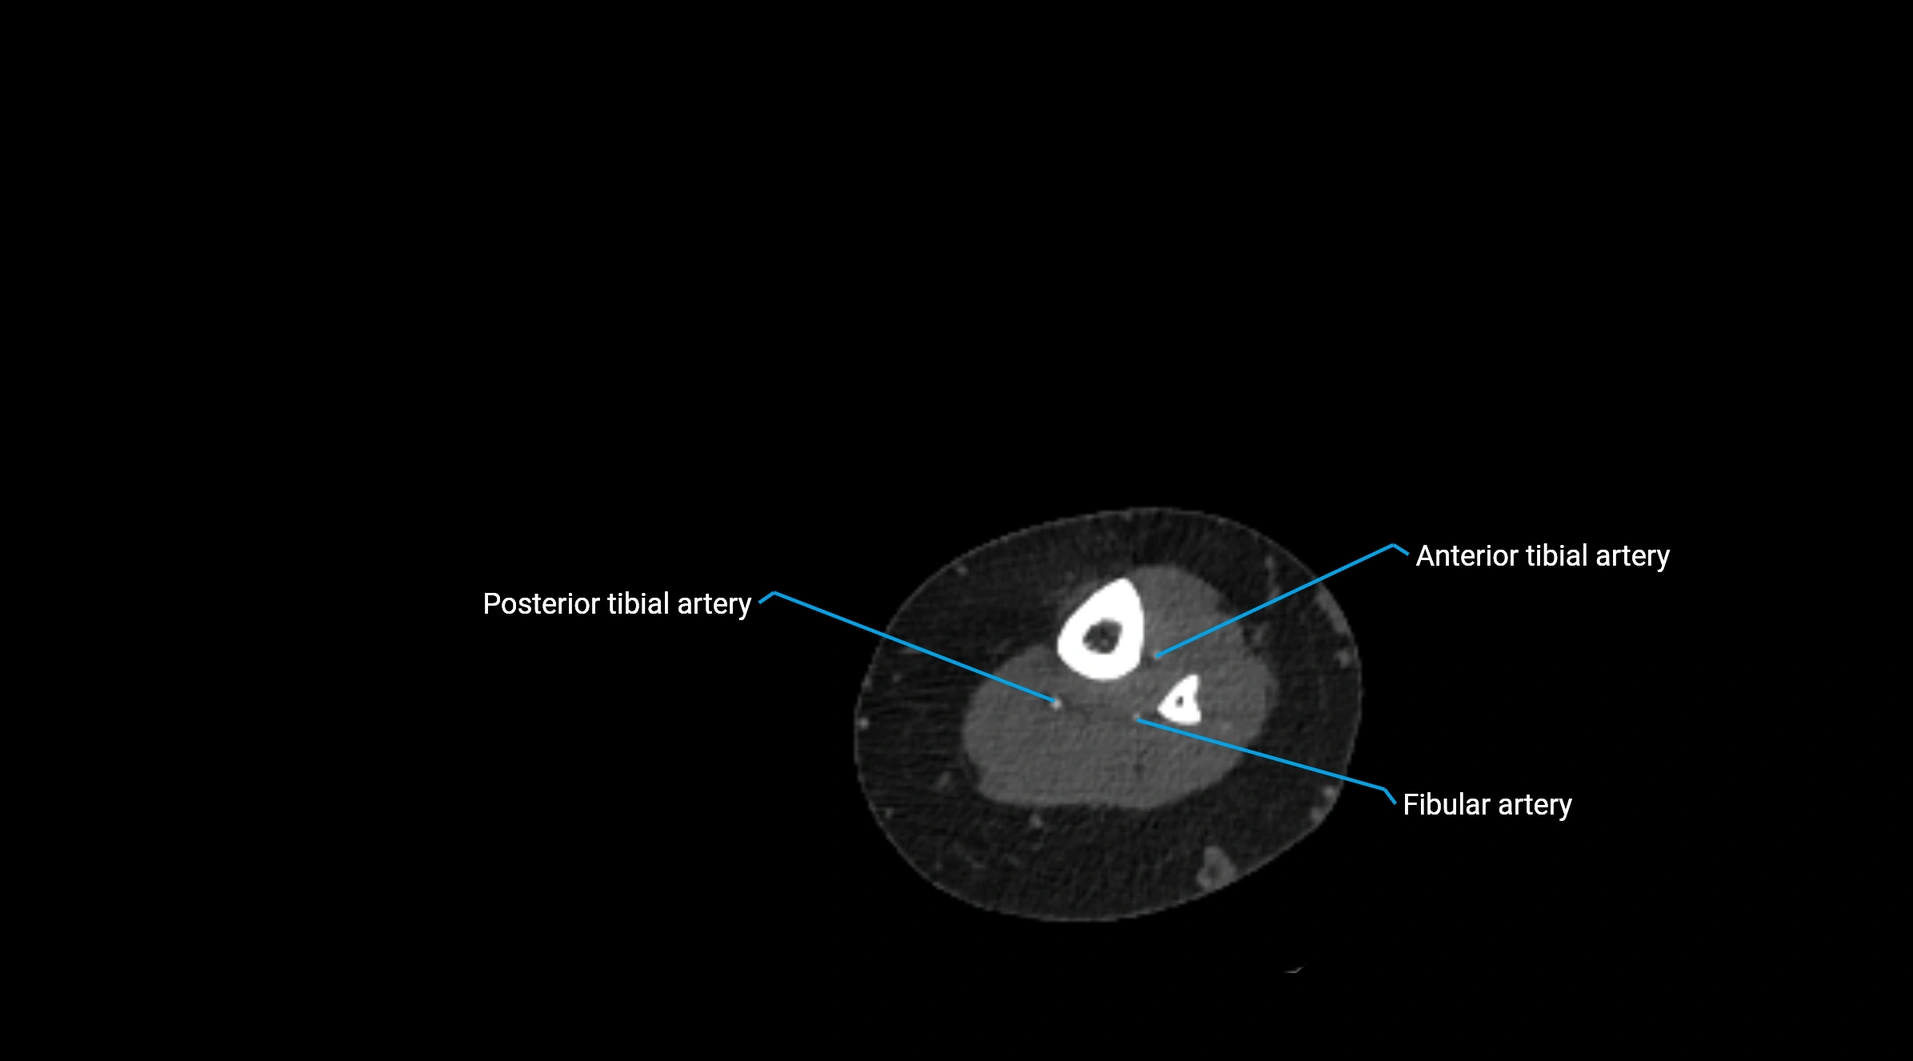

CT images

image